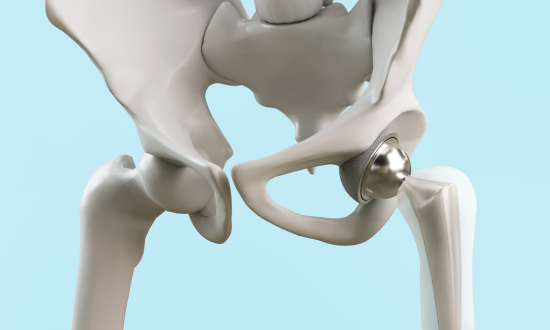

What Is Hip Replacement Surgery?

Hip replacement surgery, also known as hip arthroplasty, is a procedure that involves removing damaged portions of the hip joint and replacing them with artificial implants. This helps relieve pain, improve mobility, and restore function.